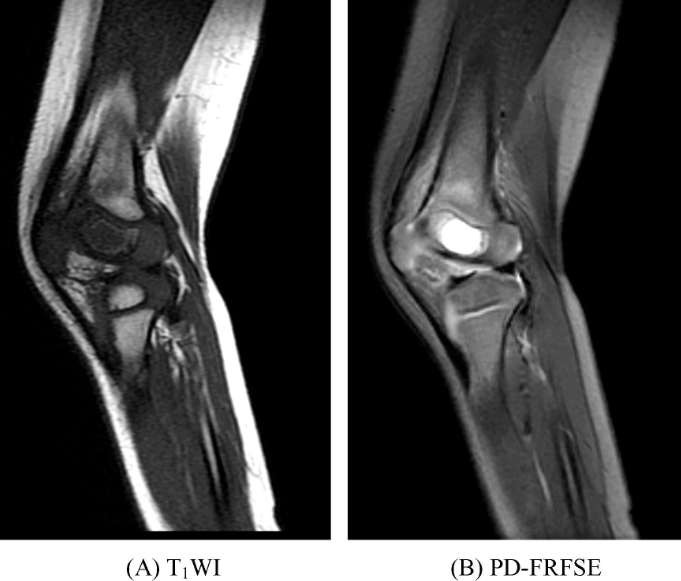

好发于骺板已闭合的四肢长骨骨端,常直达骨性关节面下,表现为膨胀性偏心性骨质破坏。肿瘤边界清楚,周围无低信号环圈。瘤体在T1WI呈均匀的低或中等信号,高信号区提示亚急性或慢性出血。在T2WI信号不均匀,呈混杂信号(图1),瘤组织信号较高,陈旧出血呈高信号,而含铁血黄素沉积呈低信号,出血和坏死液化区可出现液-液平面。一般无骨膜反应。少数可形成骨外肿块,但边界清楚,在T2WI上呈高信号。增强扫描肿瘤组织可见不同程度的强化,而坏死囊变区无强化。

图1 骨巨细胞瘤股骨远端内侧可见类圆形异常信号灶,直达关节面,边界清楚,T1WI上呈不均匀低信号,T2WI上呈高信号,内见多个囊状更高信号影,病变内侧边缘突出骨轮廓,邻近骨皮质不连续。右膝关节腔内可见带状长T1长T2信号影。